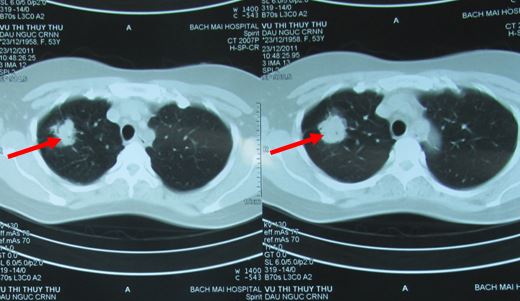

- Chụp CT scanner lồng ngực:

Hình 1: Hình ảnh chụp CT phổi trước điều trị: u phổi P kích thước 3,4cm

- So sánh trên hình ảnh CT u phổi di căn não trước và sau điều trị (ĐT)

Hình 6: U phổi trước ĐT

Hình 7: U phổi sau ĐT 16 tháng, tổn thương xơ hóa nhỏ